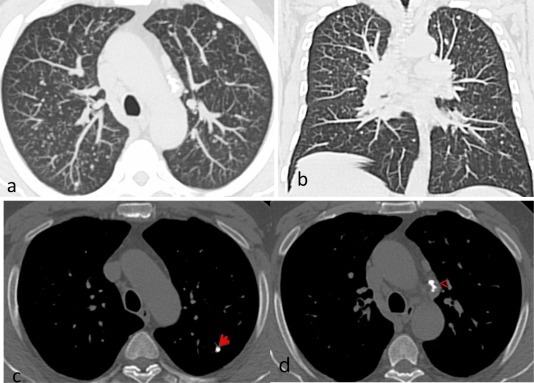

Pt also has RA and the following pulmonary findings in the image

Caplan syndrome: RA +pneumoconiosis